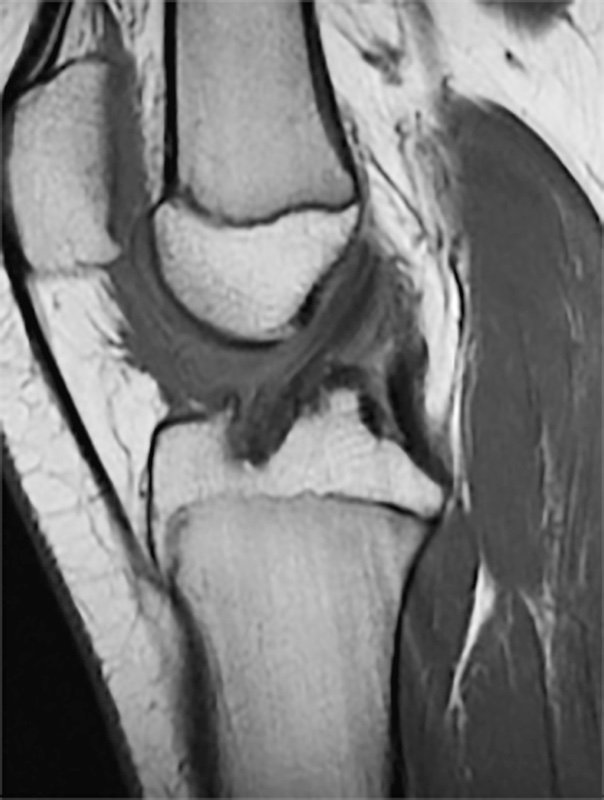

Come nella rottura del LCA negli adulti la diagnosi è prevalentemente clinica, con RX e RMN utili soprattutto nel verificare la presenza di lesioni associate.

Tecniche transfisi

La tecnica trans-fisi nel bambino è simile a quella che il chirurgo utilizzerebbe per la ricostruzione del LCA negli adulti. La ricostruzione trans-fisi a singolo fascio con semitendinoso quadruplicato è la più comune. È importante assicurarsi che il diametro dei tunnel ossei sia il più piccolo possibile (< 9 mm) per ospitare un trapianto di dimensioni adeguate. Allo stesso modo, per ridurre al minimo il danno alla fisi, orientare il tunnel tibiale il più verticalmente e centralmente possibile. Sul lato femorale, bisognerebbe fare attenzione a evitare l’anello pericondrale.

La tecnica transfisi può anche esser parziale, cioè utilizzare utilizzare una fresa a retrodrill a bassa velocità per evitare danni termici alle fisi, creando half-tunnel tibiali e femorali.

La tecnica all-inside prevede due half tunnel, uno femorale e uno tibiale. Si procede al prelievo del tendine semitendinoso o gracile.

Attraverso l’uso di guide si posizionano i fili guida tibiale e femorale. Seguendo la direzione dei fili guida si esegue la fresatura con tecnica retrograda con guida out-in del tunnel femorale e tibiale del diametro inferiore ai 4 mm. Si eseguono le misurazioni della lunghezza del tramite femorale e tibiale. Si esegue successivamente la fresatura retrograda degli half-tunnel femorale e tibiale con uno strumento specifico. Questo, già introdotto per la posizione del foro, possiede un’aletta che viene aperta una volta che lo strumento è stato inserito in articolazione. È possibile utilizzare strumenti con il diametro dell’aletta che va da 3.5 mm a 10 mm e che permette la fresatura dell’half-tunnel con tecnica in-out, ottenendo un tunnel femorale e tibiale con una lunghezza di circa 20-25 mm. Il graft viene introdotto in articolazione attraverso il portale artroscopico, passato nel tunnel femorale e fissato prima a livello femorale, quindi viene introdotto nel tunnel tibiale, tensionato e saggiato con palpatore e fissato il costrutto deve generalmente essere dai 6 ai 7 cm.